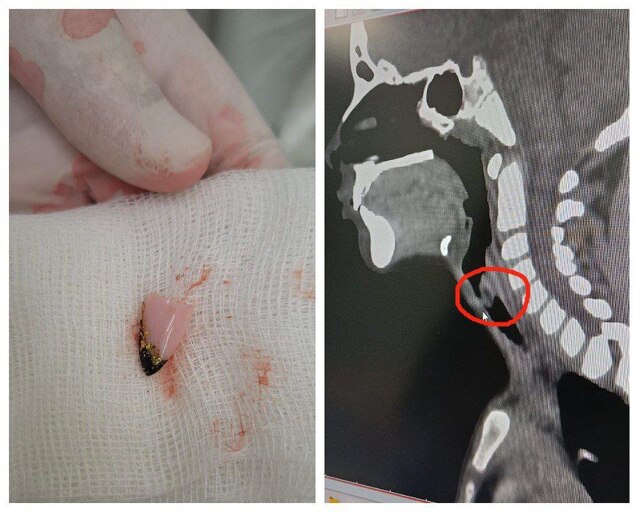

Улатӑрта тухтӑрсем 6-ри ачана экстреннӑй майпа операци туса тип пырӗнчен чӗрне кӑларнӑ.

Чӗрне ҫӑтса янӑ ачана пульницӑна илсе ҫитернӗ. Тухтӑрсем тӗрӗсленӗ хыҫҫӑн акӑ мӗн палӑртнӑ: пыра лекнӗ япала сывлав ҫулне лексе сывлӑша пӳлме е йӑлмака сие сиенлетме пултарать. Санавиаци линийӗпе Республикӑри ача-пӑча клиника больницин тухтӑрӗсем килнӗ. Вӗсем ачана пӑхнӑ хыҫҫӑн часрах операци тунӑ.

Тухтӑрсем темиҫе кун сӑнанӑ хыҫҫӑн ачана киле янӑ.